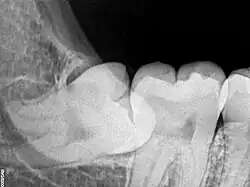

Dental x-ray of impacted lower left wisdom tooth with a horizontal orientation